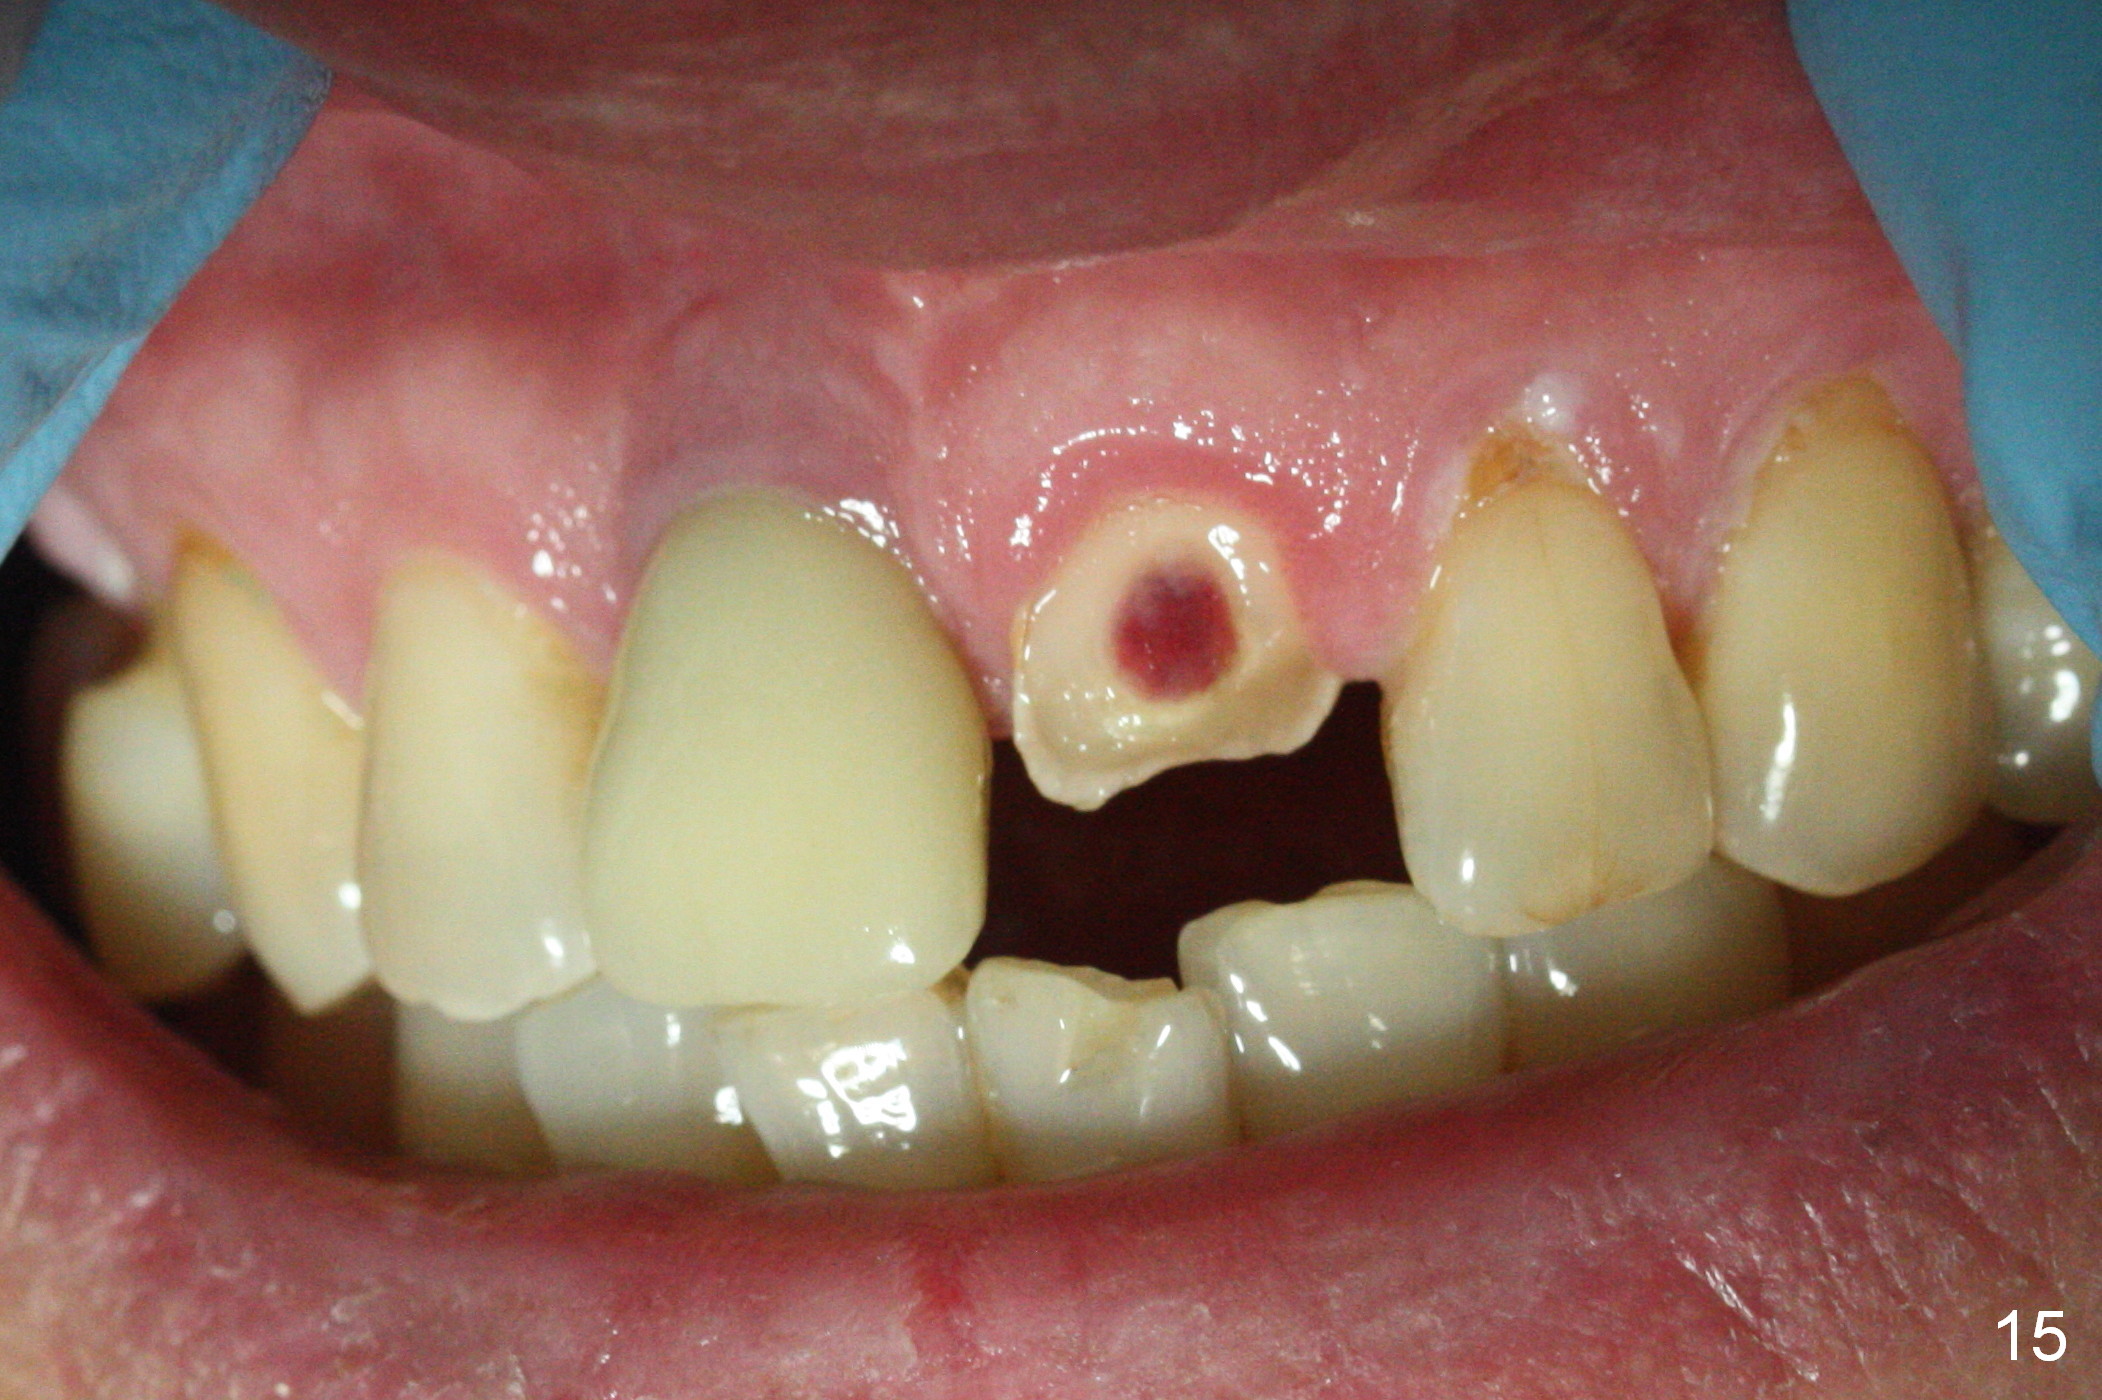

When the patient returns 3 years 10 months post cementation, the tooth #9 fractures (Fig.13,15,16), and receives root canal therapy (Fig.14). The dark gingiva could be avoided if the implant is placed more palatally and smaller in diameter (Fig.15,16).